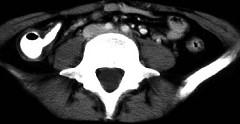

问题 女,32岁,腹痛、腹泻、便秘交替出现,粘液血便半年,里急后重,影像检查如图,最佳的诊断是 ( )

选项 A.结肠癌 B.慢性结肠炎 C.过敏性结肠炎 D.溃疡性结肠炎 E.肠结核

答案 D